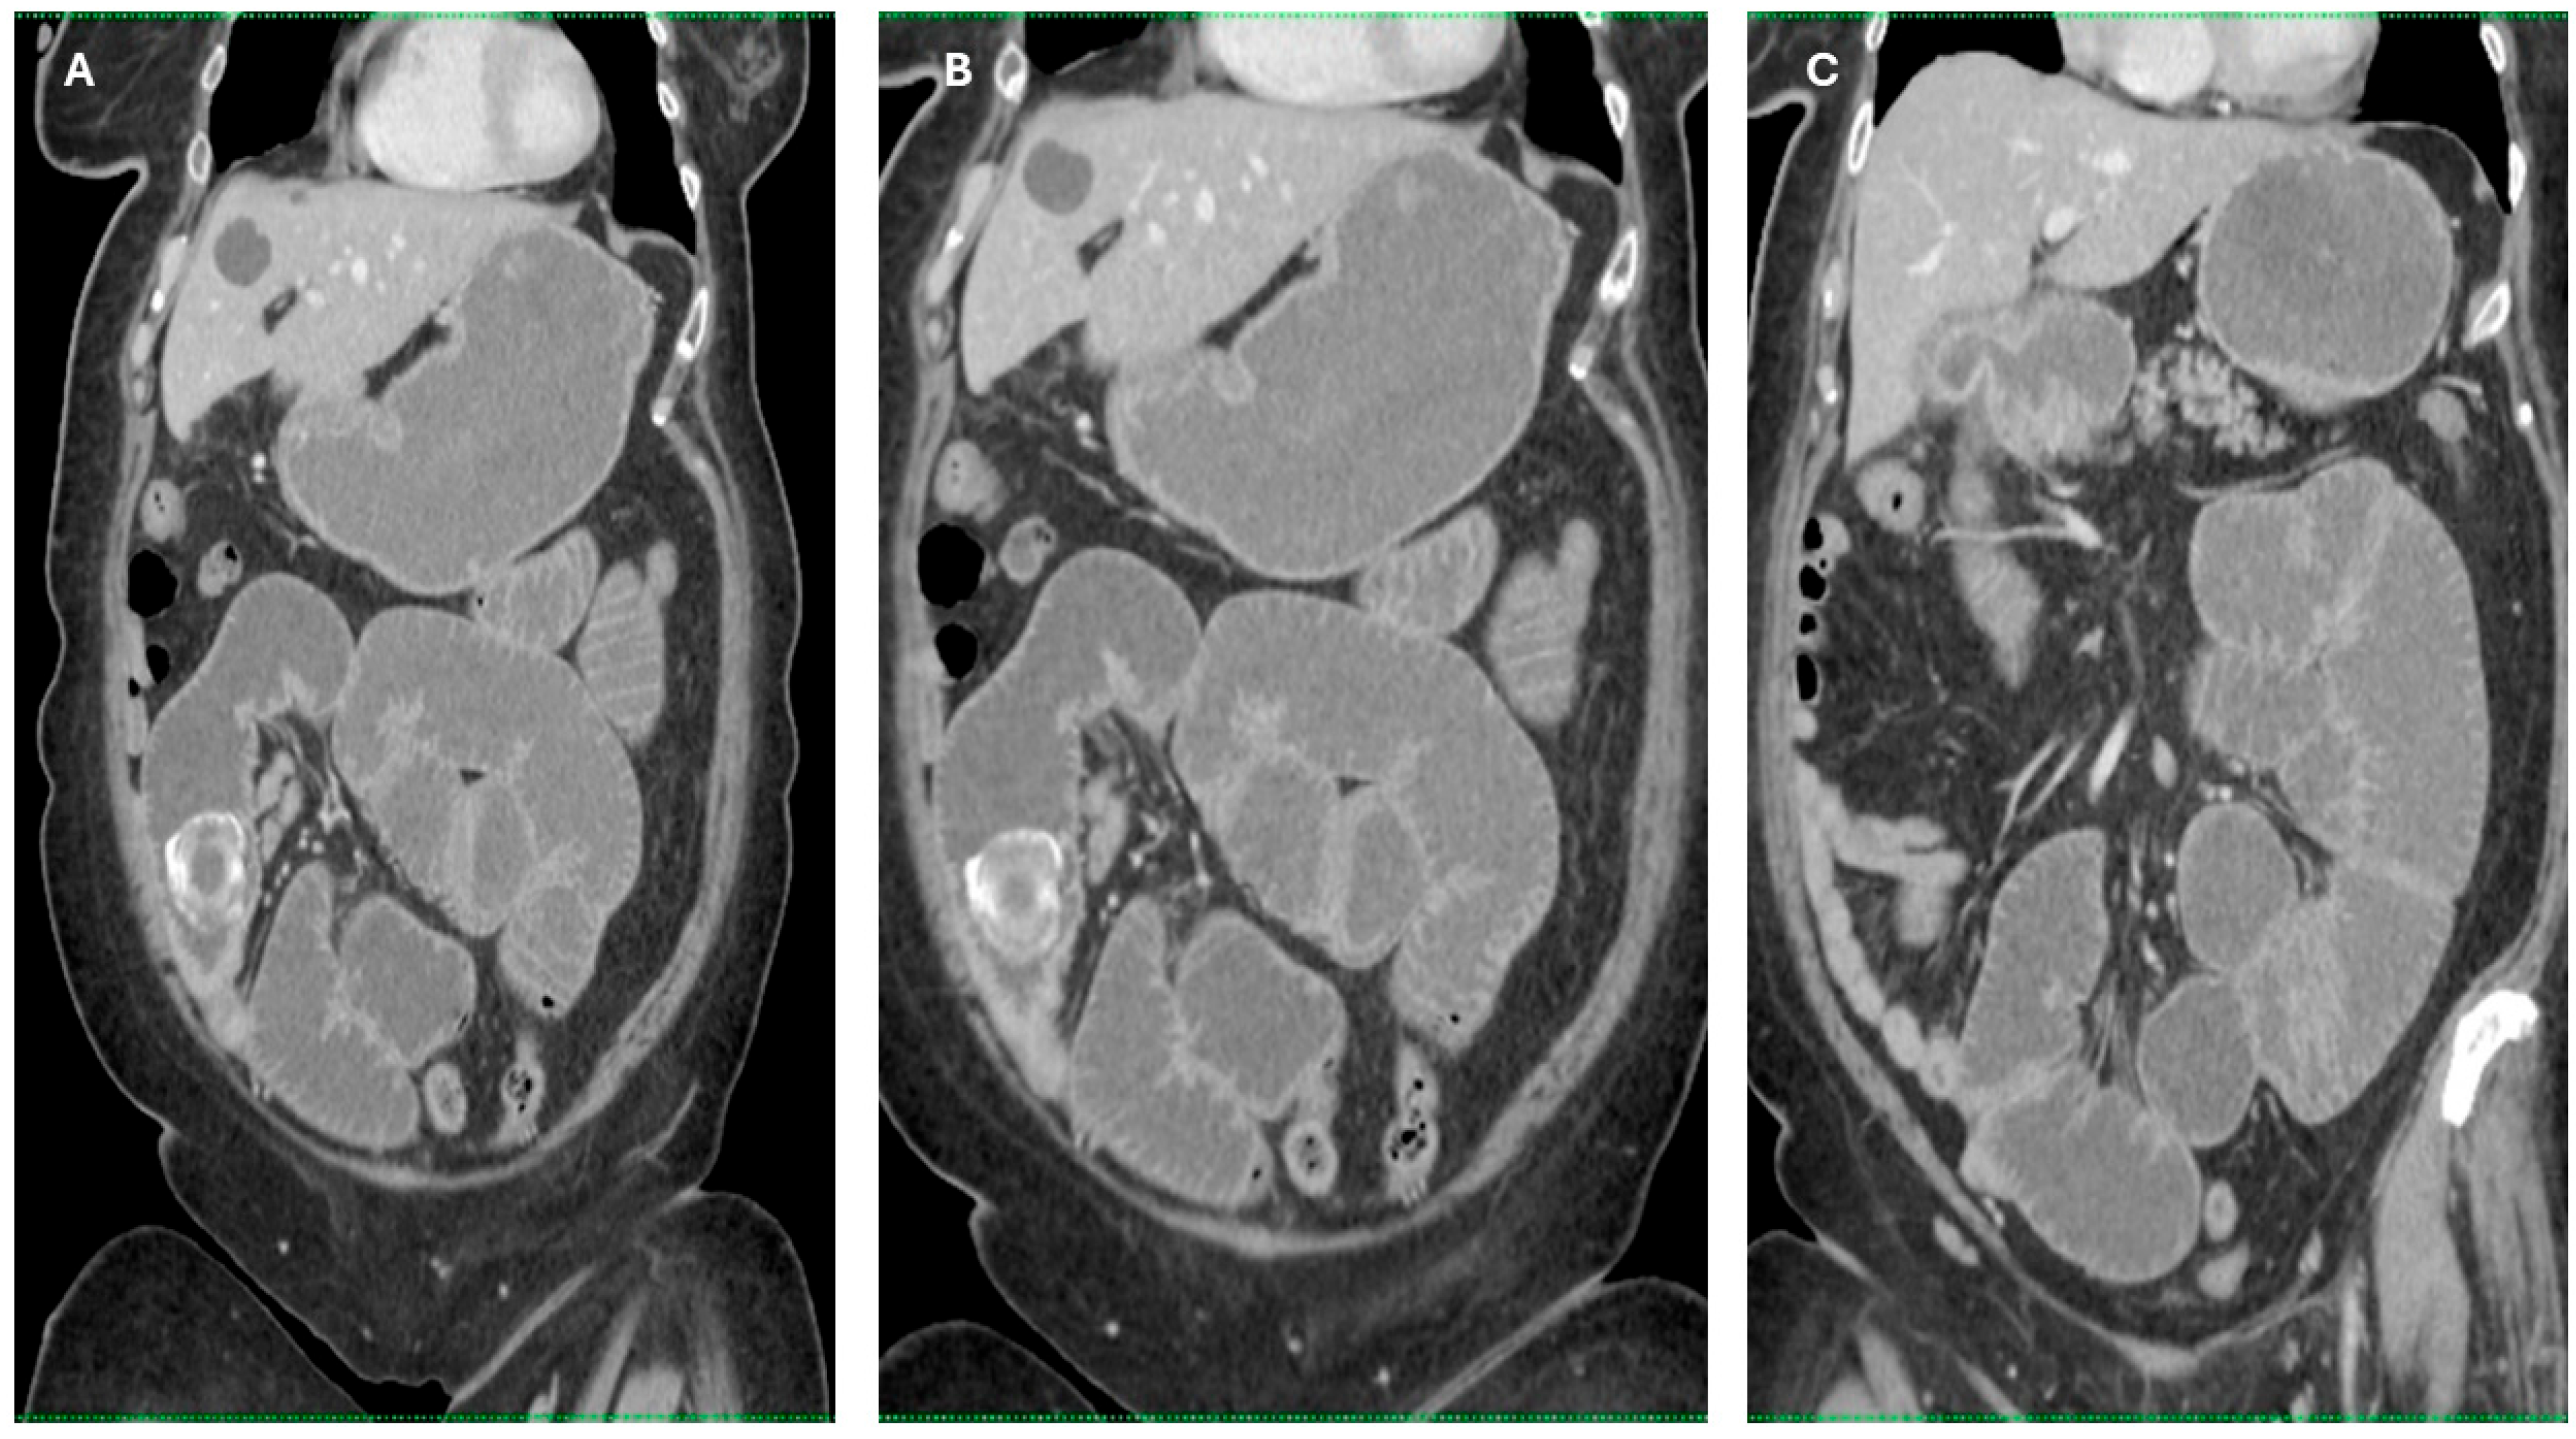

Imaging findings were consistent with biliary ileus, characterized by the presence of ectopic gallstones within the gastrointestinal tract. As shown in Figure 3A–C, axial and coronal CT images demonstrated radiopaque enteric gallstones. Figure 4 highlights a gallstone associated with a cholecystoduodenal fistula. Further axial and coronal sections (Figure 5A–C) show additional enteric gallstones, including one in the rectal ampulla.

Figure 3. Radiological features of enteric gallstones in biliary ileus. (A) Axial CT section demonstrating a highly radiopaque enteric gallstone located within the intestinal lumen, consistent with biliary ileus. (B,C) Coronal and axial reconstructed CT images further illustrating the presence of an enteric gallstone causing intestinal obstruction—features characteristic of biliary ileus. Acquisition with 5 mm slice thickness and 3 mm reconstruction. Images have been cropped and zoomed for optimal visualization while maintaining the original scale; a 10 mm scale bar is included in each panel.